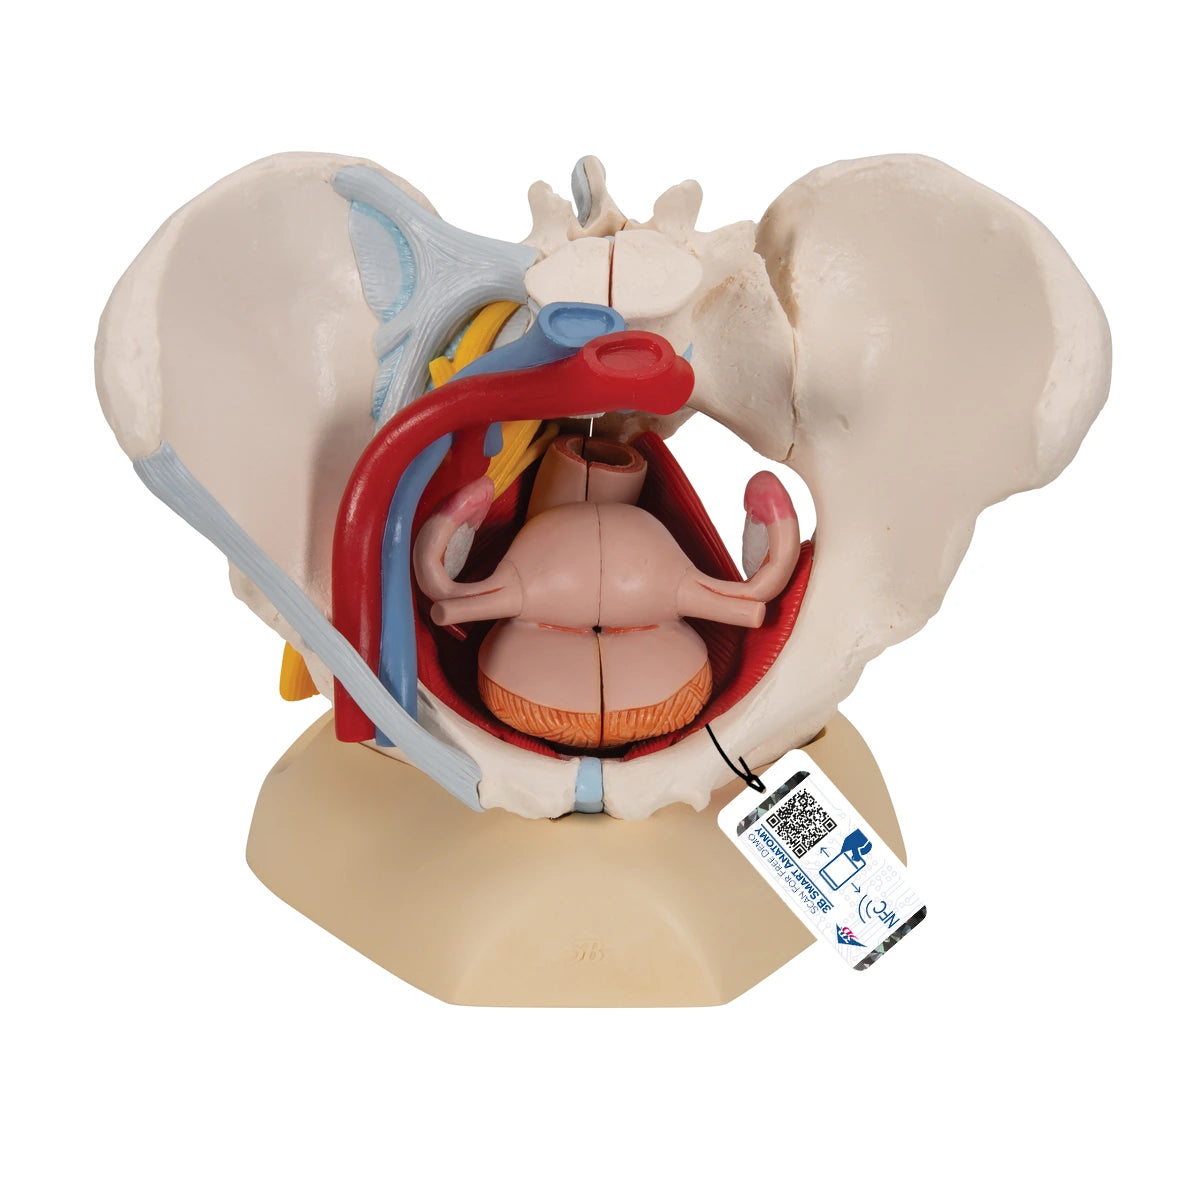

Pelvis femenina con ligamentos, vasos, nervios, piso pélvico y órganos – 6 partes

Precio de venta$30,055.26